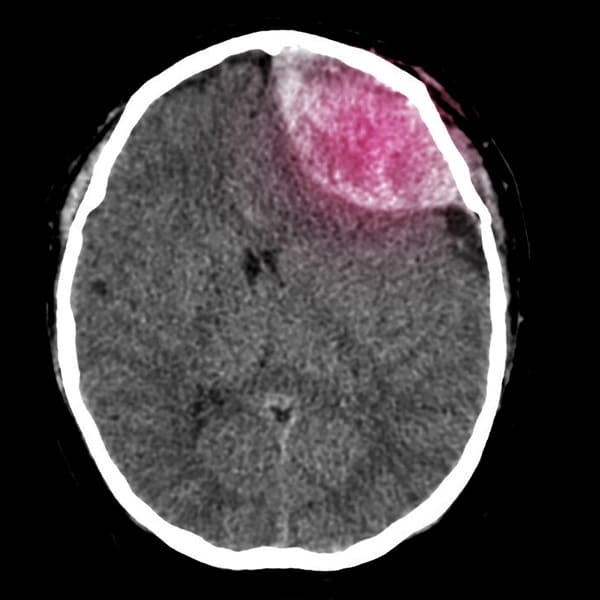

Hematomas intraparenquimatosos

Este tipo de hematoma, también conocido como hematoma intraparenquimatoso, se produce cuando la sangre se acumula en los tejidos del cerebro.

Hay muchas causas, entre ellas traumatismos, ruptura de un vaso sanguíneo abultado (aneurisma), arterias y venas mal conectadas desde el nacimiento, presión arterial alta y tumores. Las enfermedades pueden causar una fuga espontánea de sangre al cerebro. Un traumatismo craneal puede provocar múltiples hematomas intracerebrales graves.

Un hematoma intracraneal puede poner en riesgo la vida y requiere un tratamiento de emergencia.